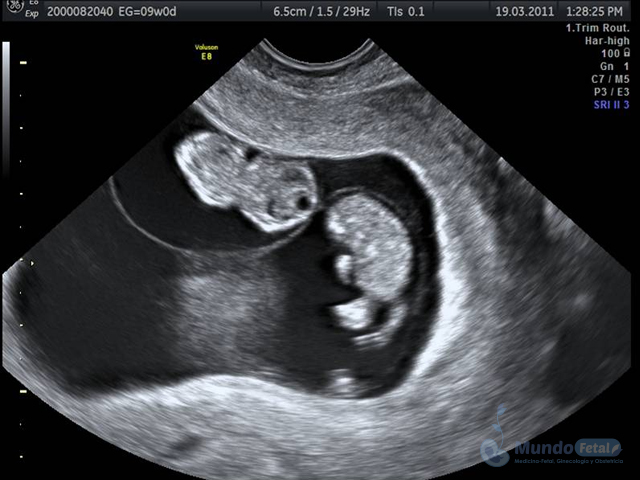

Ultrasonido Embarazo Múltiple

Es esencial detectarlo desde el primer trimestre (especialmente 11-13.6 semanas de gestación) con la intención de conocer el número de bebes, cuántas placentas y bolsas amnióticas, ya que el seguimiento de estos es distinto, esto por los riesgos que conllevan de presentar alguna alteración propia de estos embarazos, indicativos de una vigilancia estrecha y estudios complementarios, durante toda la gestación.